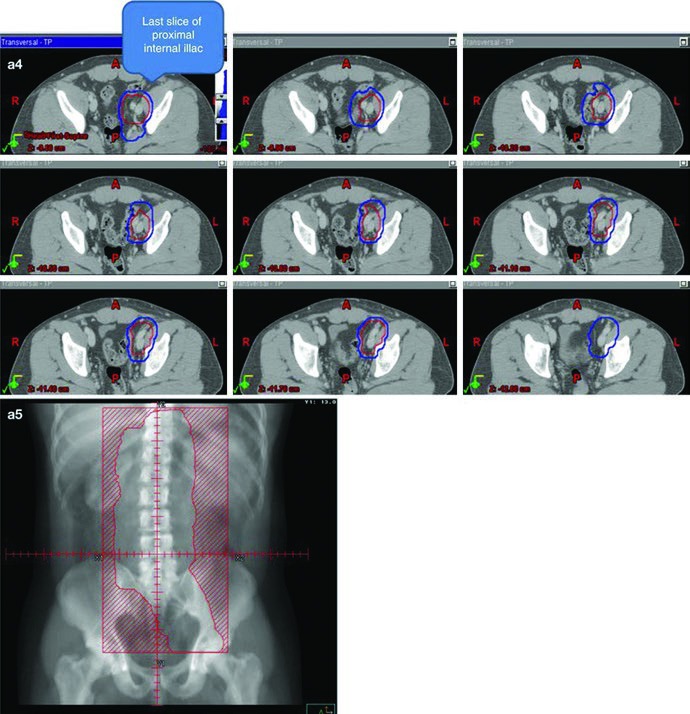

O ponto técnico mais útil é que o dogleg não nasce do zero. Ele começa com o mesmo contorno de cava inferior e aorta usado no estágio I e, em seguida, incorpora vasos ilíacos comuns, porções proximais dos ilíacos internos até a emergência da glútea superior e vasos ilíacos externos até a borda superior do acetábulo, com expansão de 1,2 cm respeitando limites anatômicos. Depois disso, o capítulo pede contorno da doença nodal grosseira, o GTV, com expansão de 0,8 cm respeitando a anatomia, formando um CTV nodal. A união do CTV vascular com o CTV nodal produz o CTV inicial.

Esse campo inicial recebe expansão de 0,5 cm mais 0,7 cm até a borda do bloco para compor o PTV inicial, ainda na faixa de 20 a 25,5 Gy com frações de 1,5 a 2,0 Gy. O boost em conedown segue a mesma lógica geométrica aplicada ao CTV nodal, também com 0,5 cm mais 0,7 cm até a borda do bloco, até completar 30 a 36 Gy em 2 Gy por fração. O capítulo ainda acrescenta uma regra simples e prática para a doença visível: garantir margem de 2 cm ao redor de toda adenopatia grosseira visível.

Os marcos anatômicos ajudam a não perder o eixo do campo. Superiormente, o limite permanece no topo de T11, com a mesma nota de que algumas fontes usam topo de T12. Inferiormente, o capítulo posiciona o limite no topo do acetábulo, embora algumas fontes recomendem o meio ou a base do forame obturatório. A borda lateral acompanha as pontas dos processos transversos das vértebras lombares, tipicamente em torno de L3, considerando a posição dos rins, e se estende inferiormente para cobrir a borda lateral do acetábulo. Para seminoma à esquerda, a cobertura do hilo renal esquerdo volta a aparecer como opcional.

A figura de boost fecha esse raciocínio muito bem. Ela mostra, em um exemplo de estágio IIA, a diferença entre GTV em amarelo, CTV em vermelho e PTV em azul. Não é só uma ilustração bonita; é a prova visual de que o capítulo separa volume eletivo, volume inicial e volume de reforço com precisão suficiente para orientar planejamento real.